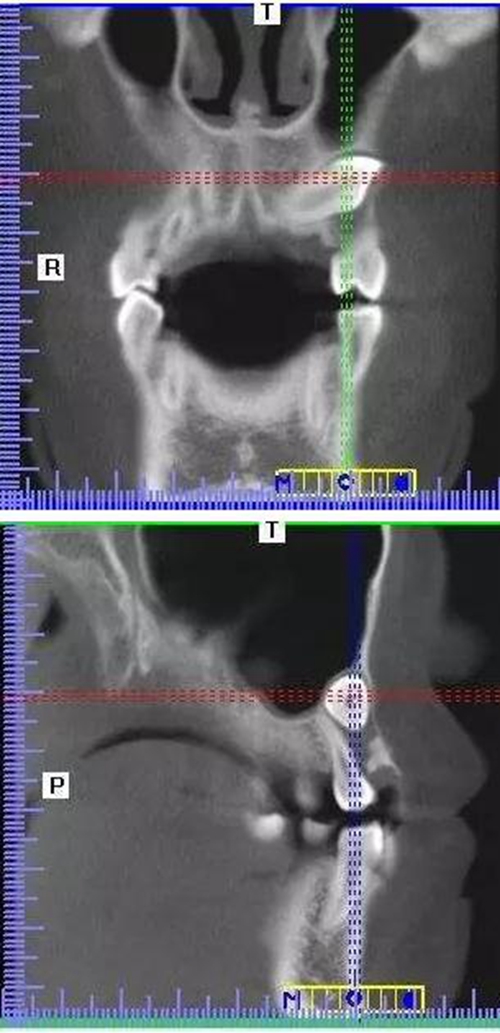

本案:患兒,女,14歲,因牙齒矯正來院,檢查見83滯留,43未見萌出,拍片發(fā)現(xiàn):43埋伏阻生于31、41、42根尖下方,按照正畸診療計(jì)劃,擬行43拔除術(shù)。

CBCT顯示